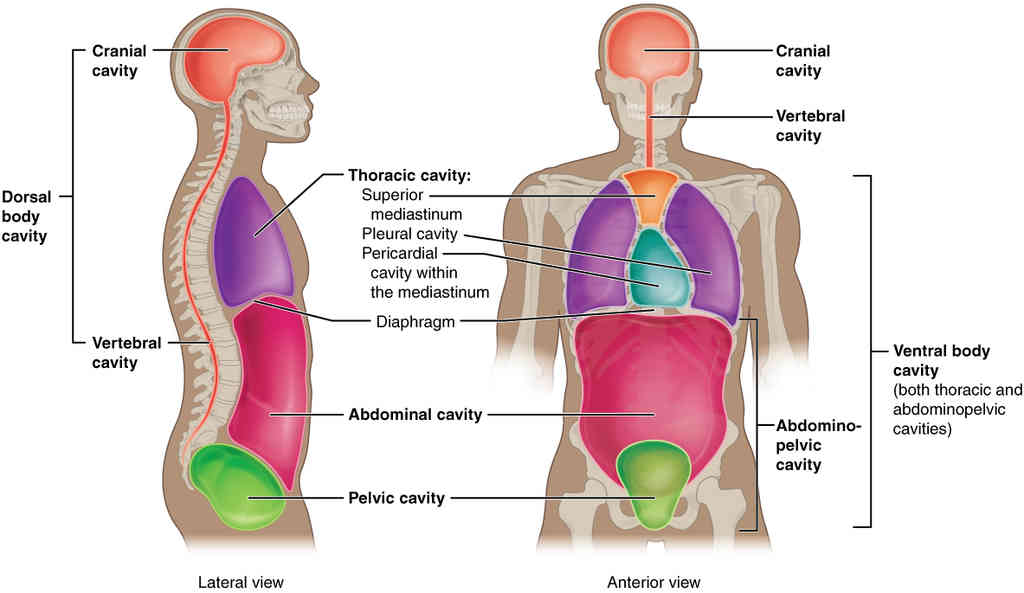

This page is under construction. For now, it is just a resource of the images found in the OpenStax Anatomy and Physiology Handbook. It wil slowly change into a revision tool. Each slide has a number. Use this to refer to the slide. When completed, it will have an unlabelled section, with labelled slides in parallel. On the unlabelled slides, write your answer and use the labelled slide to assess yourself. Keep track by also noting the number on each slide. Improvement at each attempt is important, more so than full marks on a first attempt.